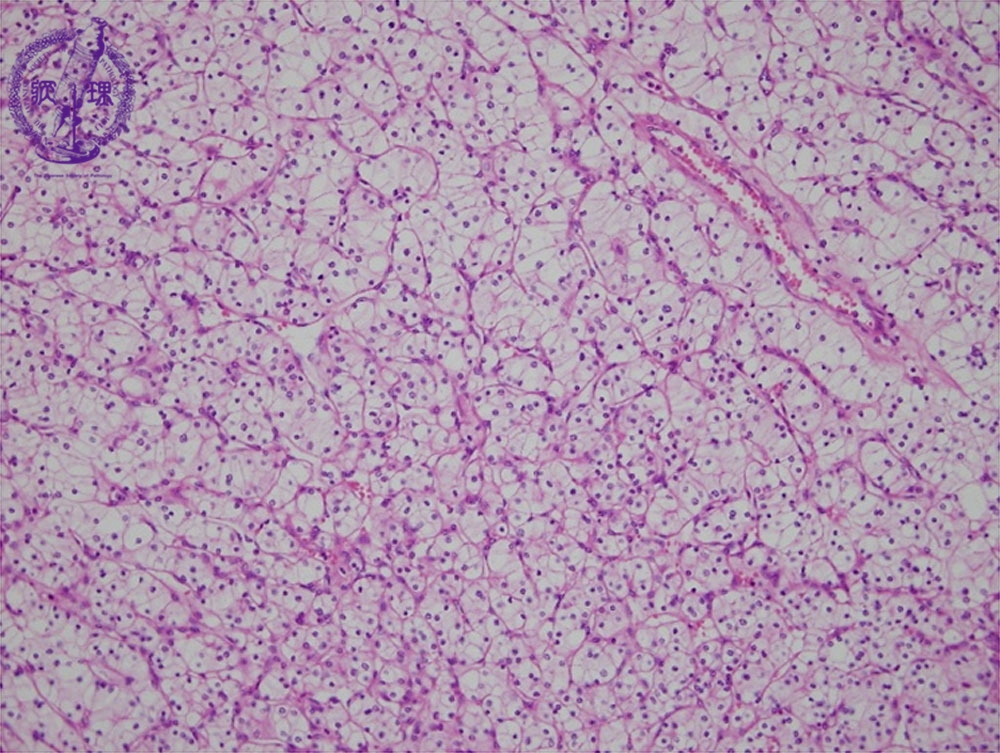

- ★(17)Renal cell carcinoma

Microscopic findings ( HE, middle power view): Renal cell carcinoma (clear cell carcinoma). The tumor cells are arranged in an alveolar manner associated with a fine sinusoid-like capillary network (red dotted lines).